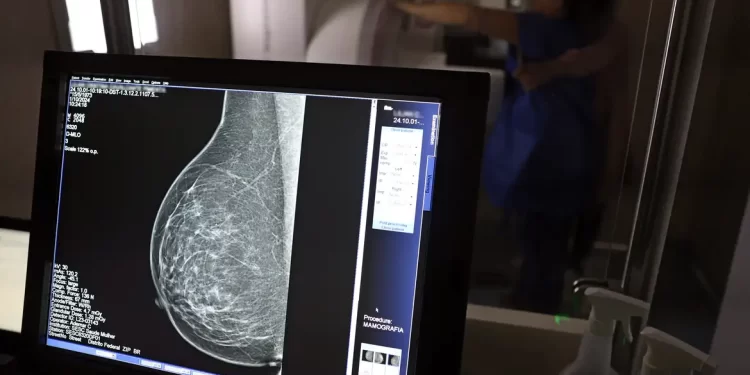

No Outubro Rosa, o Instituto Nacional de Câncer (Inca) estimou 73.610 novos casos este ano no país. É o câncer que mais mata mulheres no Brasil. As mulheres em tratamento pela doença têm o direito de receber o auxílio-doença ou o benefício de prestação continuada.

A vice-presidente da Comissão de Previdência Social Pública da Ordem dos Advogados do Brasil do Rio de Janeiro (OAB-RJ), Danielle Guimarães, destaca que o câncer de mama é uma das doenças que mais afetam mulheres no Brasil, impactando não apenas a saúde física e emocional, mas também a capacidade de trabalho e a segurança financeira das pacientes.